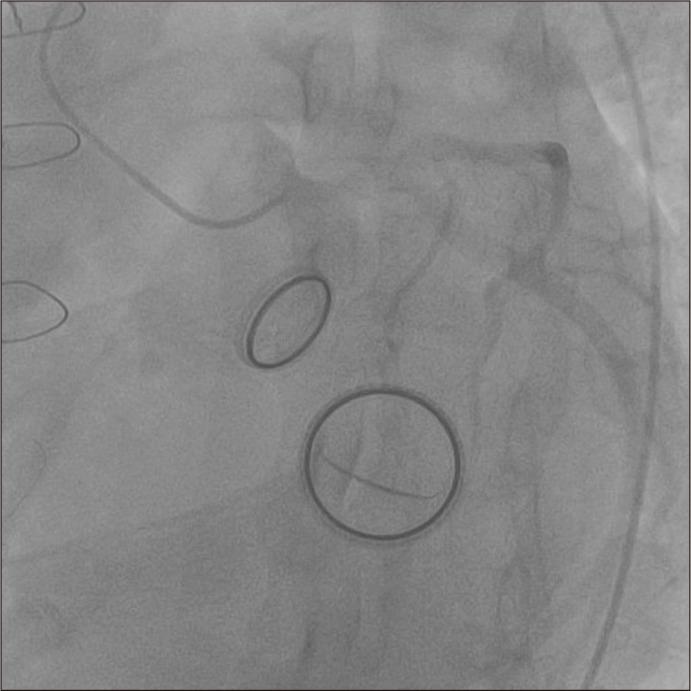

Fracture of prosthetic valve leaflets in the absence of traumatic injury is very rare. Leaflet fracture can cause acute pulmonary edema and cardiogenic shock and is potentially life-threatening, requiring emergency surgery. Thus, a leaflet fracture must be diagnosed quickly and accurately. We present the case of a 46-year-old man with CarboMedics prosthetic aortic and mitral valve replacements implanted 24 years previously. The patient presented at our emergency department with abrupt dyspnea and fever. We diagnosed severe mitral valve regurgitation with anterior leaflet fracture. The patient underwent venoarterial extracorporeal membrane oxygenation and delayed mitral valve replacement. The foreign body was removed step by step because the diagnosis was missed. Two pieces of broken leaflets were found in the left common iliac artery and left external iliac artery. The patient was treated successfully and remains asymptomatic 1 year following surgery.

在无创伤性损伤的情况下,人工瓣膜小叶骨折非常罕见。小叶骨折可导致急性肺水肿和心源性休克,有潜在生命危险,需要紧急手术。因此,必须快速准确地诊断小叶骨折。我们报告一例46岁男性病例,其24年前植入了CarboMedics人工主动脉瓣和二尖瓣。该患者因突发呼吸困难和发热就诊于我院急诊科。我们诊断为严重二尖瓣反流伴前叶骨折。患者接受了静脉-动脉体外膜肺氧合及延迟二尖瓣置换术。由于漏诊,异物被逐步取出。在左髂总动脉和左髂外动脉中发现了两片破碎的小叶。患者治疗成功,术后1年无症状。